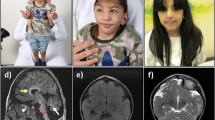

This boy is the first child to healthy unrelated parents of Kurdish origin. Apart from transiently decreased fetal movements reported by the mother (during 7th months of pregnancy), the pregnancy was uneventful. The boy was born after 37 weeks of gestation with a birth weight of 2630 g, length of 49 cm and head circumference of 32 cm. The Apgar score was 10-10-10 and the perinatal period was uncomplicated. The boy was first admitted at 9 months of age because of bilateral esotropia. He was then also found to have hyperopia (+7-8). Regular ophthalmological investigation revealed no other changes. He was again admitted at 13 months of age because of delayed psychomotor development. He could sit, grasp with his whole hands and move between them and babbled with two syllables, corresponding to a developmental age of around 6–7 months. Muscle tone and tendon reflexes were normal. He learned to say a few words and to walk unsupported around 3 years of age. His communicative skills peaked at 5 years of age when he could combine 2–3 words, while his best motor function was at 9 years of age when he could walk unsupported both uphill and downhill. He has since then slowly lost developmental skills and has become increasingly stiff. A trial of L-Dopa treatment had no effect. A permanent gastrostomy was placed at 11 years of age because of swallowing difficulties although he still managed to eat small pieces of food by himself. At the last assessment at 16 years of age, he was a very happy and easy-going young man with the ability to communicate with gestures, sounds, pointing and about 30 signs and a few words. He was able to walk around 100 m with support and had a comparably good fine motor function with bilateral pincer grasp. On examination he had generally increased muscle tone considered to be a mixture of spasticity and rigidity with associated contractures in large joints and a right-sided scoliosis. The muscle tendon reflexes were generally increased with left-sided ankle clonus and a right-sided Babinski’s sign. There were no involuntary movements or signs of ataxia. He had no seizures and EEG was normal. Head circumference and height has been normal and there were no signs of additional organ involvement. Routine laboratory investigations including metabolic screening analyses have been normal. A 3 T MRI of the brain was performed at 8 years of age showing mild features of hypomyelination and thinning of corpus callosum (Fig. 1). In view of the unusual phenotype, further investigation of the SLC17A5 gene was driven by the elevation of free sialic acid in urine and fibroblasts.

Axial T2 sequences showed slightly increased T2 signal in supratentorial central white matter (a) while the cerebellar white matter looked normal (b). Axial T1-weighted imaging showed normally signaling supratentorial white matter (c). Sagittal T2-weighted imaging revealed a somewhat thin corpus callosum and a small cyst (1.2 cm) of the corpus pineale (d)

The lysosomal free sialic acid storage disorders present with a broad clinical spectrum. Salla disease represents the mildest phenotype and occurs most frequently in Finland, and other Nordic countries such as Sweden and Denmark [7, 8, 18, 19]. The infantile form of sialic acid storage disease shows a more severe clinical phenotype and has no geographic predominance [7, 20, 21]. There also exists SASD forms that are intermediate in severity between Salla and ISSD [22–26]. Whereas Salla patients usually present with hypotonia, ataxia and nystagmus the first year of life, our patient showed delayed psychomotor development together with hyperopia at age 3 years. Ataxia usually remains a prominent feature as Salla disease progresses, however in the present case ataxia has not incurred. Instead, our patient shows increased muscle tone, most likely due to a mixture of spasticity and rigidity. The only clinical symptoms overlapping with Salla disease are in fact early psychomotor retardation and speech problems, which by itself is not very disease specific. MRI findings further support the milder clinical phenotype with weak features of hypomyelination and thinning of corpus callosum in contrast to Salla patients where cerebral and cerebellar atrophy, hypomyelination and corpus callosum hypoplasia are typical findings. Thus, the patient described in this paper shows an even milder clinical phenotype of SASD than Salla disease, which makes it difficult to pinpoint the correct diagnosis. Our findings suggest that analysis of free sialic acid needs to be considered in patients with encephalopathy and mild hypomyelination and thinning of corpus callosum.